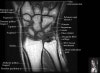

- Sagittal section

Sagittal T1 evaluates the tendons, bone marrow and relationships between the osseous structures.